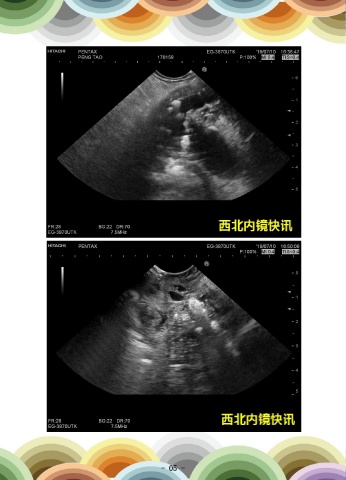

入院后行超声内镜示:胰腺体尾部实质萎缩,胰管增宽,约5mm,腔内多枚结石影,

直径3-8mm,最大一枚嵌顿于胰头,见胰腺头部低回声增大,截面直径31x27mm,胆总

管壁中段及下段增厚,最厚1.7mm,管腔狭窄,上段扩张明显,直径约1.2cm。换用十二

指肠镜观察乳头,正常结构消失,表面糜烂渗血,活检质软。